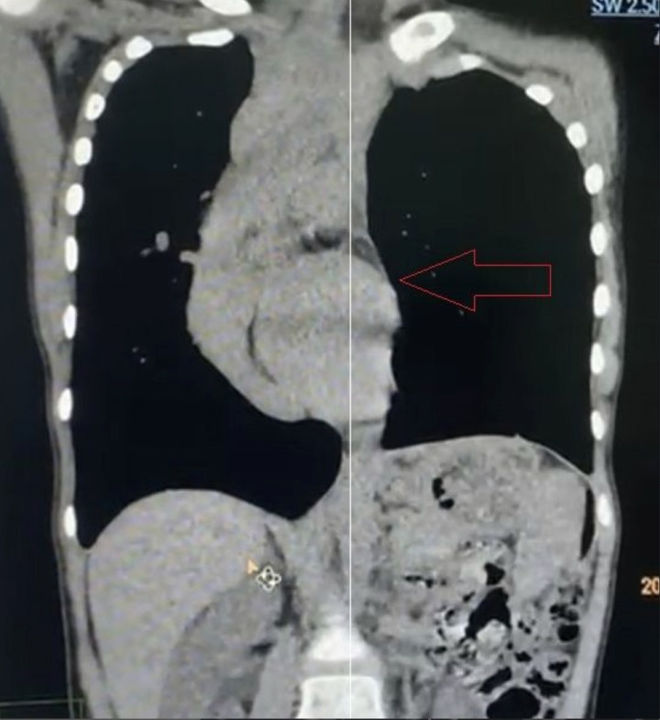

The anterior chest wall shows a severe asymmetric depression, causing marked compression of the heart, which is displaced toward the right thoracic cavity. The patient also presents with scoliosis. She is diagnosed with malignant pectus excavatum.

In clinical practice, when a depression develops in the chest wall and exerts pressure on the heart, the heart is more likely to be displaced to the left due to its normal anatomical position. Rightward displacement of the heart is extremely rare and, when present, often indicates significant cardiac compromise, putting the patient at high risk of developing serious symptoms. Based on these considerations, the chest wall deformity in this case was classified as malignant pectus excavatum, necessitating prompt surgical intervention.

The surgery for this case was highly challenging. Given the significant cardiac compression, two major intraoperative risks were present: first, the patient was at risk of sudden cardiac arrest when lying supine, necessitating immediate correction of the deformity to relieve cardiac compression and ensure patient safety. Second, due to the severe and asymmetric nature of the chest wall depression, the risk of intraoperative cardiac injury was markedly increased, and conventional surgical techniques alone would be insufficient to achieve an optimal corrective outcome.